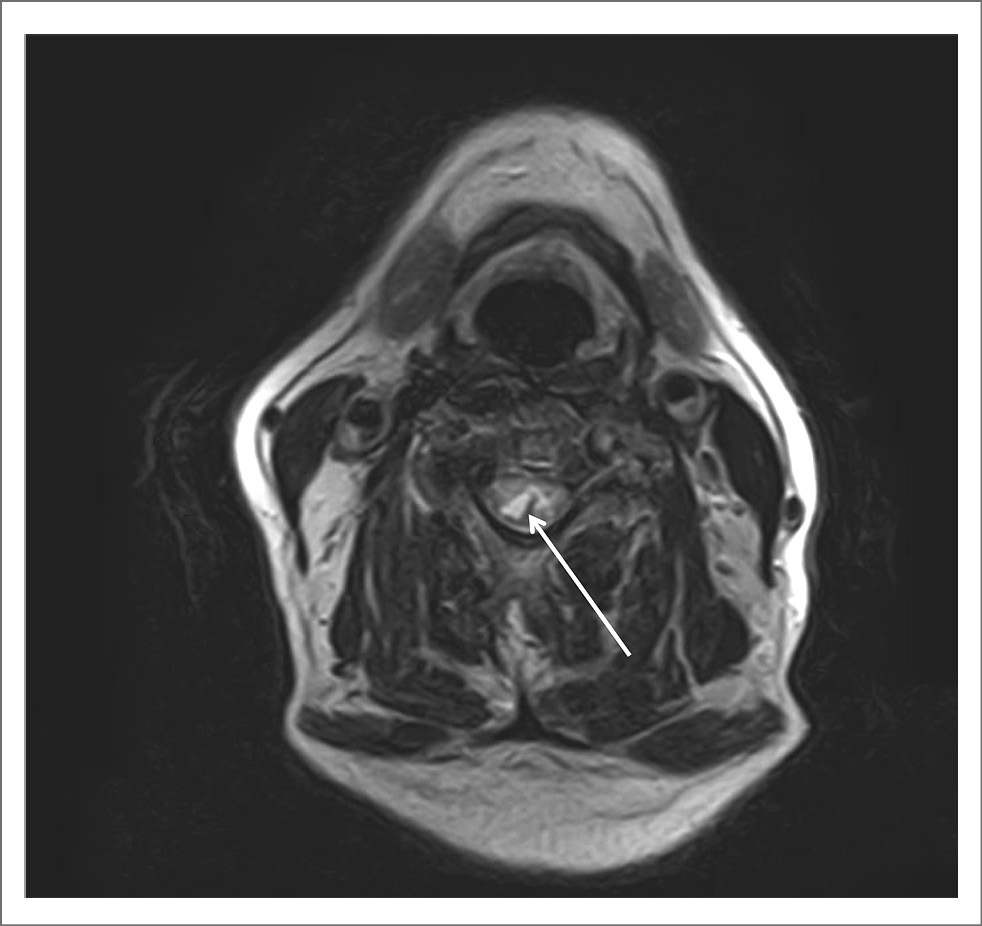

Для уточнения диагноза провели МРТ ГМ и спинного мозга. При исследовании ГМ отмечены единичные мелкие очаги в белом веществе и небольшие зоны лейкоареоза, отражающие микроангиопатию. МРТ-исследование спинного мозга в режимах T2-взвешенного изображения и FLAIR выявило протяженные участки повышенного МР-сигнала (на уровне шести шейных позвонков), заметное утолщение и неоднородную структуру шейного отдела спинного мозга, вероятно, воспалительного генеза (рис. 1, 2). При внутривенном контрастном усилении определялось накопление контрастного вещества в левом зрительном нерве на всем его протяжении (рис. 3) и в белом веществе спинного мозга, преимущественно в области задних столбов с переходом на нижнезадние отделы продолговатого мозга – зона аrea postrema (рис. 4).

Рис. 2. Изменения в шейном отделе спинного мозга на Т2-взвешенных изображениях в аксиальной проекции (показано стрелкой).

Клинические проявления миелита при ОНМ чаще всего описывают как синдром полного поперечного поражения спинного мозга, распространяющийся более чем на 3 позвонка. Однако не исключается возможность и частичного поперечного повреждения спинного мозга [4, 10]. Такая избирательность не может не отразиться и на клинической картине миелита. У нашего больного ведущими были гипертонус в мышцах шеи, плечевого пояса, нарушение суставно-мышечного чувства в руках с гиперкинезами в кистях, напоминающих хореоатетоз. МРТ-исследование выявило парциальное вовлечение в патологический процесс задних столбов на шейном уровне с преимущественным повреждением клиновидных пучков Бурдаха (см. рис. 2). Эти канатики являются проводниками глубокой чувствительности от рук, плечевого пояса и шеи, а также несут неосознаваемые проприоцептивные импульсы от заднего спинно-мозжечкового тракта к коре червя мозжечка через его нижнюю ножку [24].